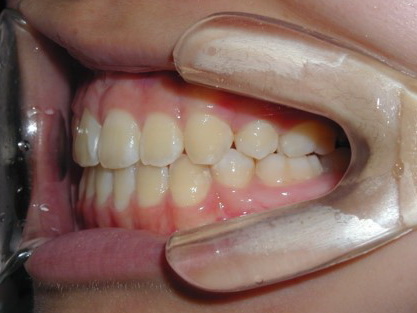

上顎の劣成長 (成長不足) による反対咬合で、上顎は拡大装置と上顎前方牽引装置を併用し前方方向への成長を促して前歯の咬み合わせを改善した後に、上下顎の前歯をマルチブラケット装置で並べました。治療の期間は2年でした。

初診時